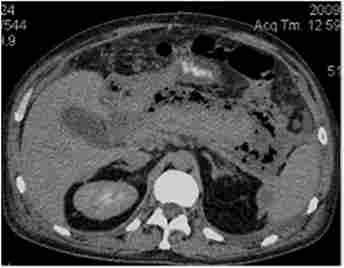

Комп'ютерні томограми хворих гнійно-некротичним нарапанкреатітом різного ступеня поширеності

Мал. 19.1. Комп'ютерні томограми хворих гнійно-некротичним нарапанкреатітом різного ступеня поширеності:

а - тип З - гнійно-некротичні тканини навколо підшлункової залози в межах електронні сумки; б - тип D зліва - поширення по паракольной клітковині зліва; в - тип D праворуч - поширення по паракольной клітковині справа; г - тип Е - поширення по паракольной клітковині зліва і справа